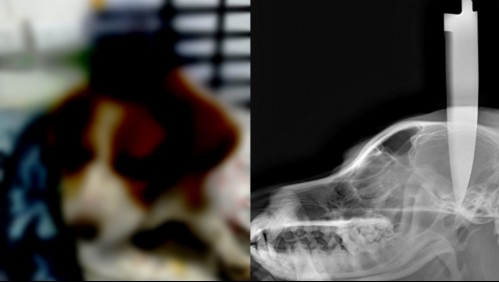

Nacional Brutal caso de maltrato animal: Enterraron un cuchillo en la cabeza a un perro y veterinario dice "nunca vi algo así"